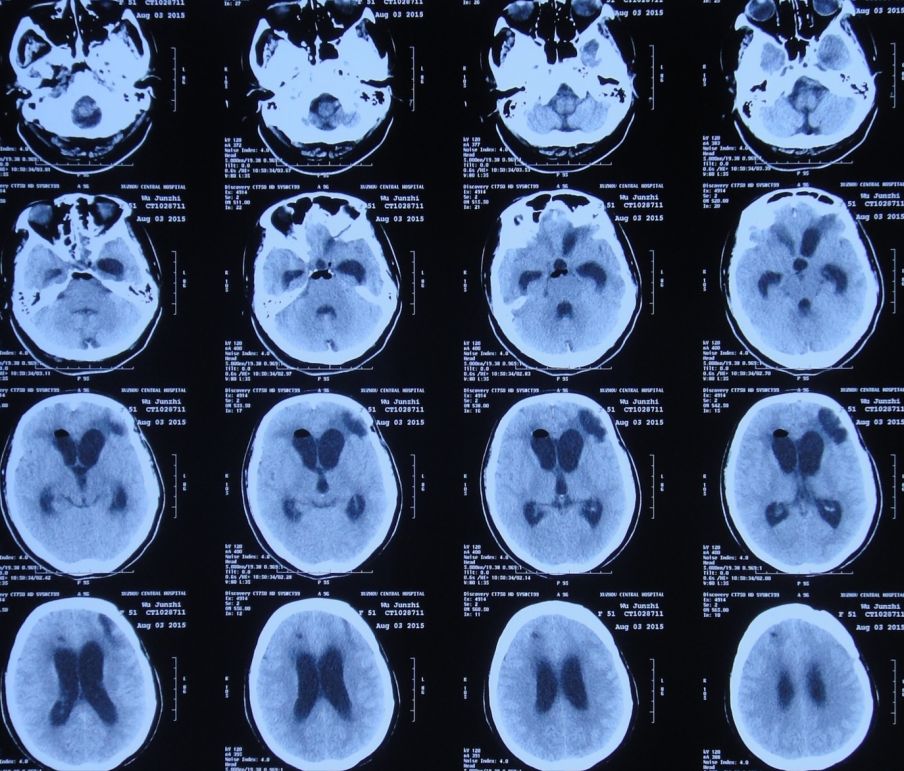

2015年7月27日患者突发高热,体温高达39.0 ℃,伴呕吐,意识转差,腰椎穿刺颅内压力极高,并留取脑脊液进行细菌培养;复查头CT检查显示脑室系统显著扩张,颅内积气(图11)。当日急诊进行了右侧侧脑室钻孔引流术,术后入住ICU给予重症监护、抗炎、抑酸等治疗。

![]()

图11:2015年7月27日头CT:脑室系统显著扩张,颅内积气

脑室引流术后第2天即2015年7月29日,患者神志恢复清楚,但仍有发热;复查头CT:脑室引流术后,脑室较前缩小(图12)。2天前腰穿留取的脑脊液细菌培养结果为白色假丝酵母菌,对氟康唑敏感,给予抗炎、抗真菌治疗。

图12:2015年7月29日头CT:脑室引流术后,脑室较前缩小

脑室引流术后第5天即2015年8月1日,患者体温恢复至正常,复查头CT:脑室扩张程度较引流术后减小(图13)。

图13:2015年8月1日头CT:脑室引流术后,脑室轻度扩张

当地医生认为长期保留头部侧脑室外引流管易导致颅内感染,故拔出了头部侧脑室外引流管。